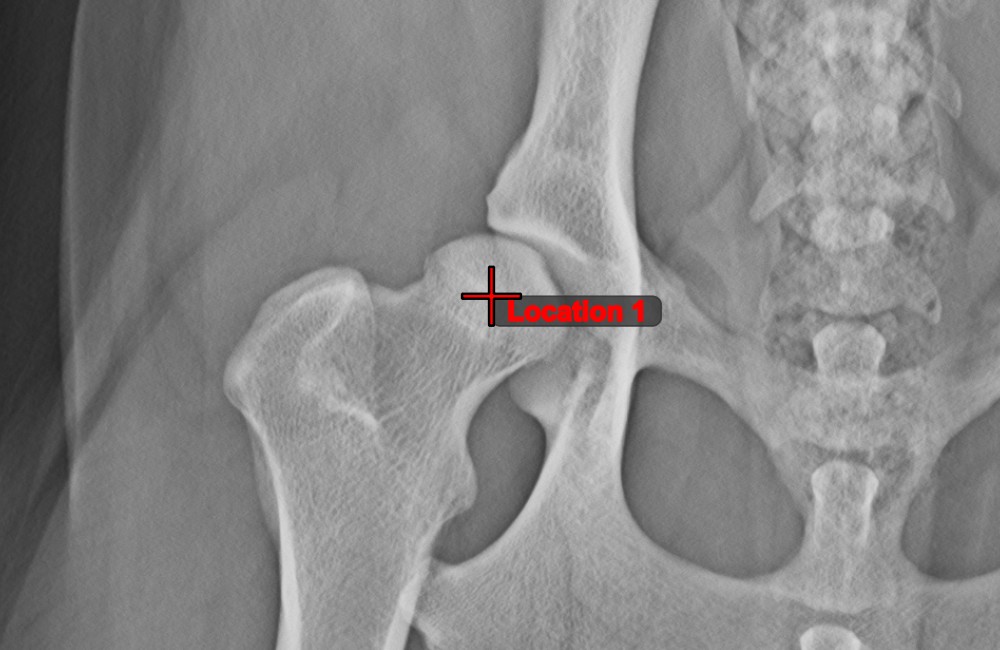

Messpunkt¶

Measurement Point

. Jeder Punkt ist zur besseren Identifizierung mit einem Buchstaben versehen.Objekt auswählen/verschieben

. Wählen Sie den Punkt mit der zugewiesenen Maustaste des Werkzeugs aus und verschieben Sie ihn dann frei an eine beliebige Stelle im Bild.